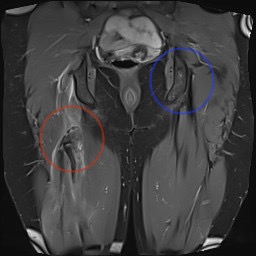

MRI

Proximal hamstring avulsion on right - red circle is retracted hamstring tendon, blue circle is normal insertion on left